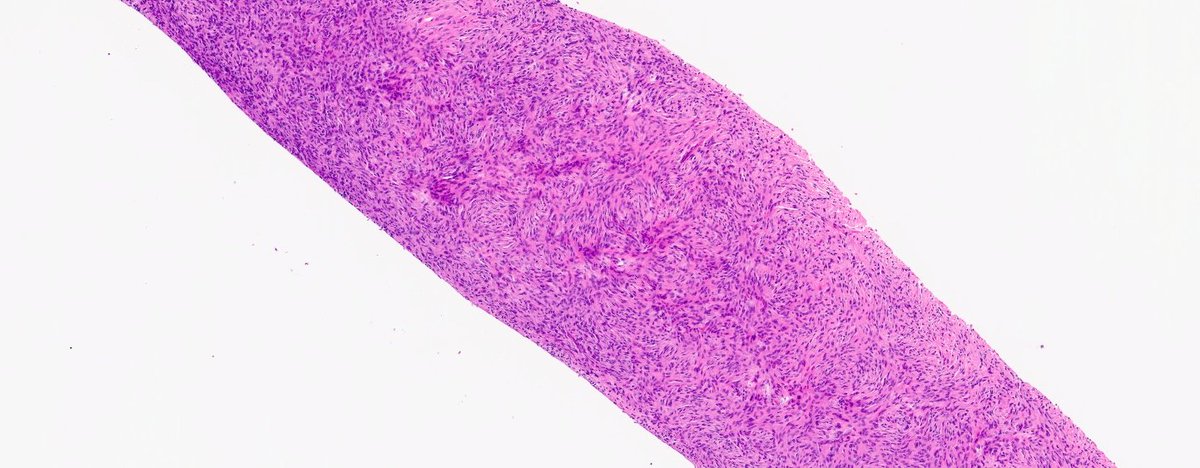

#PathQuiz what is the diagnosis? 🔬 NAB2-STAT6 🔬 hemangiopericytoma-like vessels 🔬patternless pattern @UMichPath #BSTPath #COTW

Patternless pattern - still mesmerizing.

🫁Solitary Fibrous Tumor of Lung - Rare fibroblastic neoplasm of lung with NAB2-STAT6 gene rearrangement - Patternless pattern / Hemangiopericytoma pattern with intervening keloidal collagen - Positive for CD34 and STAT 6 (highly specific) #MHPathology #cwru #PathX #pathology